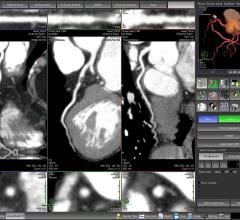

Researchers using coronary computed tomography angiography (CCTA) found no association between light to moderate alcohol consumption and coronary artery disease (CAD), according to a study presented at the 2016 annual meeting of the Radiological Society of North America (RSNA).

Philips announced the introduction of Illumeo, a new imaging and informatics technology with adaptive intelligence that enhances how radiologists work with medical images. The intelligent software is the first, according to the company, to combine contextual awareness capabilities with advanced data analytics to augment the work of the radiologist. Its built-in intelligence records the radiologists' preferences and adapts the user interface to assist the clinician by offering tool sets and measurements driven by the understanding of the clinical context.